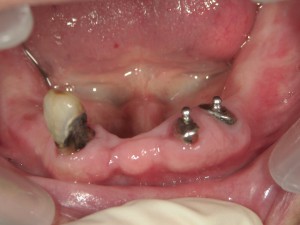

左のように歯茎の近くが酸蝕されますのでご注意くださいね♥